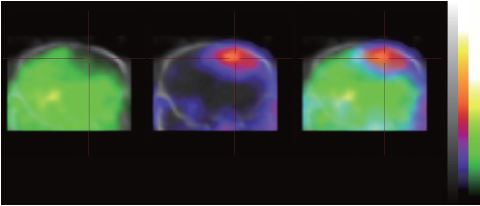

マウス脳血液関門(BBB) デュアルアイソトープ同時イメージング

99mTc-DTPAジエチレントリアミン五酢酸テクネチウム(紫)と201Tl-DDCジエチルジチオカルバミン酸塩塩化タリウム(緑)の同時検出 (横断面ビュー)

Images Courtesy of CROmed and NIVIC